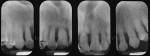

Halinen et al detected increased amounts and activity of neutrophil-derived matrix metallopeptidase-8 in patients with T21 compared to age-matched controls.20 Another strong link is found with juvenile periodontitis. The two groups have the same pattern of tissue destruction (Figure 6) and a problem with neutrophil chemotaxis. Lavine et al in 1979 found 86% of patients with juvenile periodontitis exhibited significant inhibition of PMN chemotaxis with no change in phagocytic capacity.21 Other arguments for the parallels between the two groups are based on their bacterial constitution and viral co-infections, which are explored in this article.

The clinical and radiographic appearance of periodontitis in the patient with T21 often resembles the pattern of bone loss observed in localized juvenile periodontitis (LJP). A study by Modéer found that the first signs of periodontitis may be seen as early as 11 years of age, with most lesions detected in the mandibular incisors.22 Other affected teeth include the maxillary and mandibular first molars; canines are the least affected. In general, patients with T21 are known to have a higher plaque index and increased tooth mobility.23,24 Cutress found patients with T21 presented with more bone loss compared with other individuals who had intellectual limitations in the same institution. Others have reported patients with T21 have poor circulation and hormonal disturbances.25